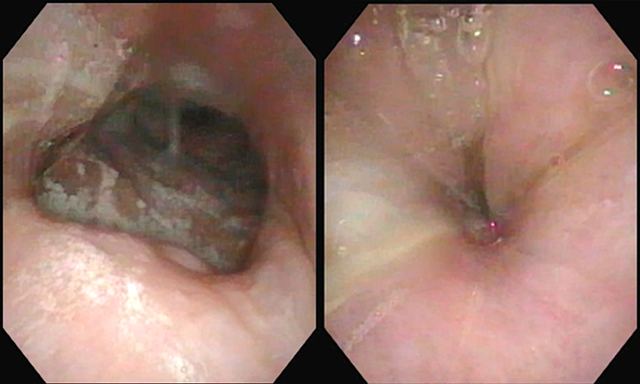

상기도 개통성은 VOTE 분류에 따라 평가한다. V(Velum), O(Oropharynx), T(Tongue Base), E(Epiglottis) 각각의 상기도 분절의 기도 폐쇄 또는 허탈의 심각도를 반영하여 점수를 매긴다. 가이드라인들에서는 50%이하의 붕괴되는 경우를 0, 50-75%이하 붕괴되는 경우는 1, 75%이상 붕괴되는 경우 2점으로 스코어링 하도록 권유하지만, 실제 경험해보면 이보다 심한 폐쇄일 때 생리적으로 폐쇄효과가 나타날 것으로 보여 이에 대한 기준은 관찰자마다 조금 다를 것으로 생각된다. 예) velum에서만 VOTE Score II인 환자

A. velum concentric II